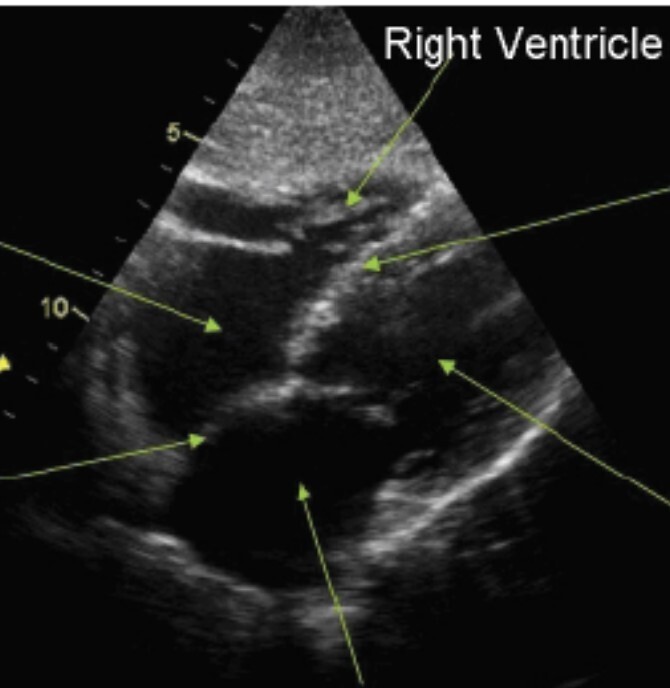

Subcostal long axis view - start 1-2 cm below the xiphoid, shift probe slightly to the right. LV, LA, RV, RA. Can ask patient to take a breath to improve image. Good for exams during cardiac arrest.